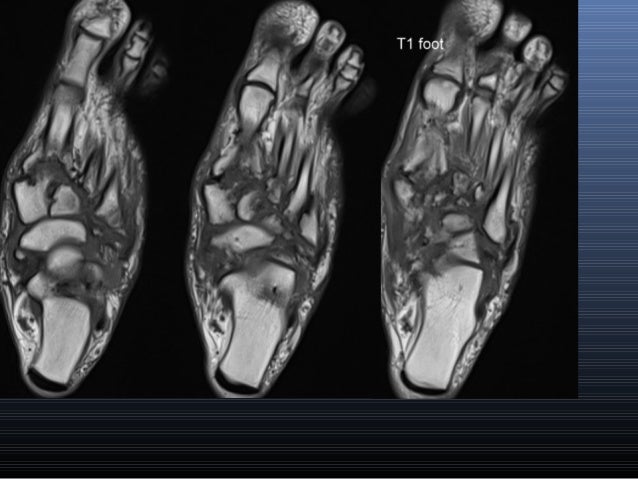

Magnetic resonance imaging (mri) is the modality of choice in diagnosing accessory muscles, delineating their relationship to adjacent structures, and differentiating them from soft tissue tumors. Routine ankle magnetic resonance imaging (mri) tests involve taking images of the foot and ankle in the axial, coronal, and sagittal planes parallel to the tabletop(2). They are considered voluntary muscles. Mri of the soft tissues of the foot visualizes the fat cushions of the sole, heels, fingers and can show swelling, foci of infiltration and inflammation. Foot muscles mri anatomy / plantar tendons of the foot mr imaging and us radiographics / neuropathies around the elbow joint.

MRI ankle - Google Search from i.pinimg.com Mri is the choice of modality for further imaging the ankle and foot after obtaining initial radiographs. Accessory muscles are isointense to skeletal muscle on all pulse sequences, and can insert by fleshy muscular or tendinous insertions. 12 photos of the foot muscle anatomy mri.magnetic resonance imaging (mri) is the modality of choice in diagnosing accessory muscles, delineating their relationship to adjacent structures, and differentiating them from soft tissue tumors. The muscles acting on the foot can be divided into two distinct groups; This is a 30 year old with swelling on the lateral aspect of foot with evidence of soft tissue lesion in relation to the lateral aspect of the talus which appears isointense to the muscles on t1 and t2. The majority of soft tissue lesions in the foot and ankle are benign. Start studying mri procedures foot/ankle review. Mri with user outlined plantar intrinsic and extrinsic muscles group.